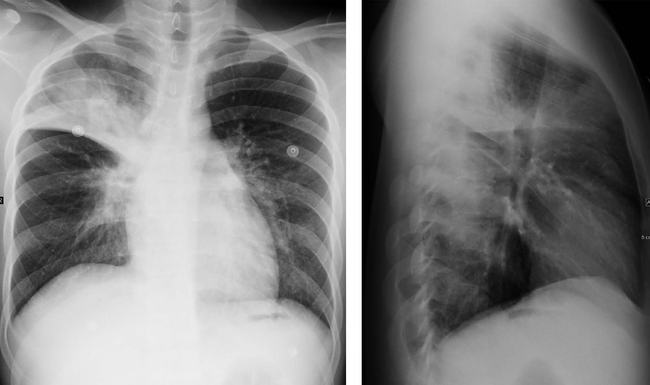

肺炎x线图片,肺炎ct图片

《春季病例回顾 教科书式大叶性肺炎一例

大叶性肺炎x线图片

大叶性肺炎x线表现